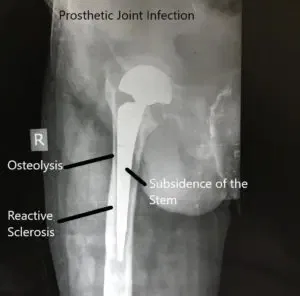

El diagnóstico de la infección de reemplazo articular implica una multitud de investigaciones relacionadas con aspiraciones radiológicas, sanguíneas y articulares. El cirujano ortopédico consultor realiza una evaluación completa de la articulación y las condiciones de salud del paciente.